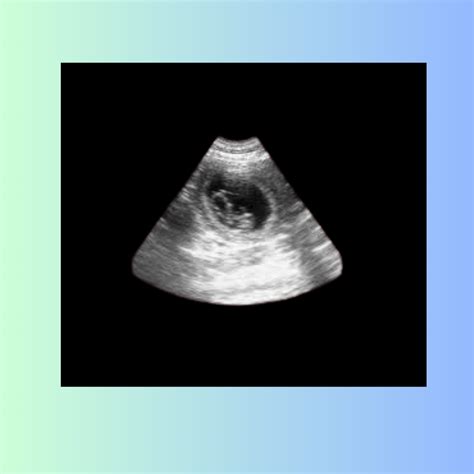

During a 7 week pregnancy sonography, the ultrasound technician will look for several key indicators of fetal development. These include:

• The presence of a gestational sac, which is the earliest sign of pregnancy visible on ultrasound.

• The yolk sac, which provides early nutrition to the embryo.

• The embryo itself, which should be visible as a small, curved structure within the gestational sac.

• The fetal pole, which is the earliest visible part of the embryo.

• The heartbeat, which may be detectable by this week, although it is not always visible at 7 weeks.

If the heartbeat is not detected, it is not necessarily a cause for concern, as it can sometimes be too early to see. The technician will also measure the size of the gestational sac and the crown-rump length (CRL) of the embryo, which helps to estimate the gestational age and ensure that the pregnancy is progressing normally.